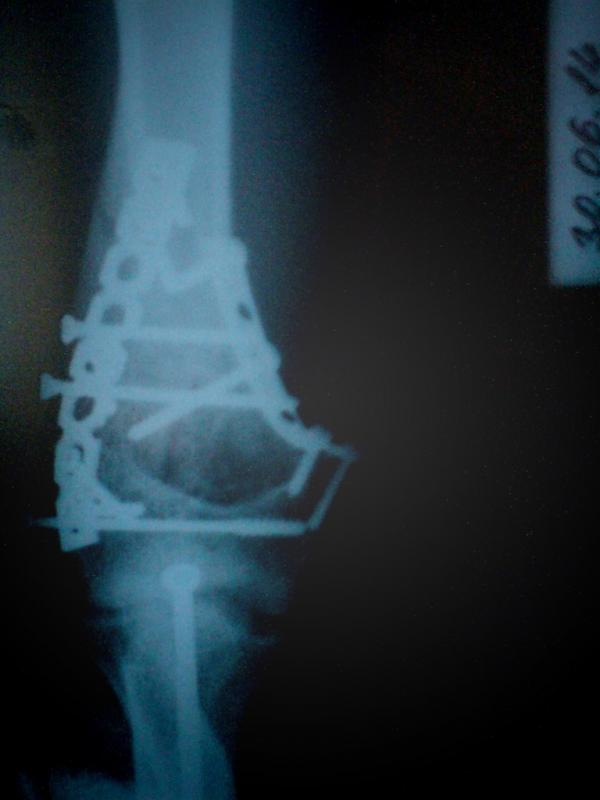

Главная > Железки > Поломки и падения

оскольчатый чрезмыщелковый перелом дистального отдела левой плечевой кости со см.отломков + оскольчатый перелом дистального метаэпифиза левой лучевой кости со см.отломков :3

в этом году закрыл сезон пораньше =(